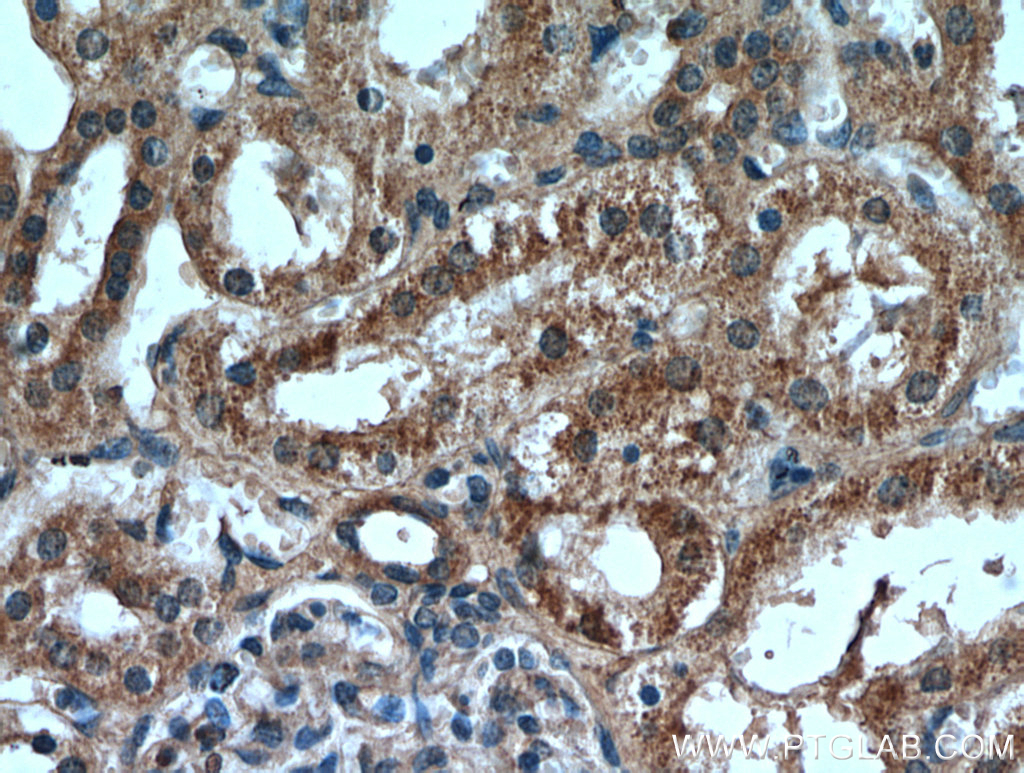

| Positive IHC detected in | human breast cancer tissue, human kidney tissue Note: suggested antigen retrieval with TE buffer pH 9.0; (*) Alternatively, antigen retrieval may be performed with citrate buffer pH 6.0 |

| Immunohistochemistry (IHC) | IHC : 1:20-1:200 |